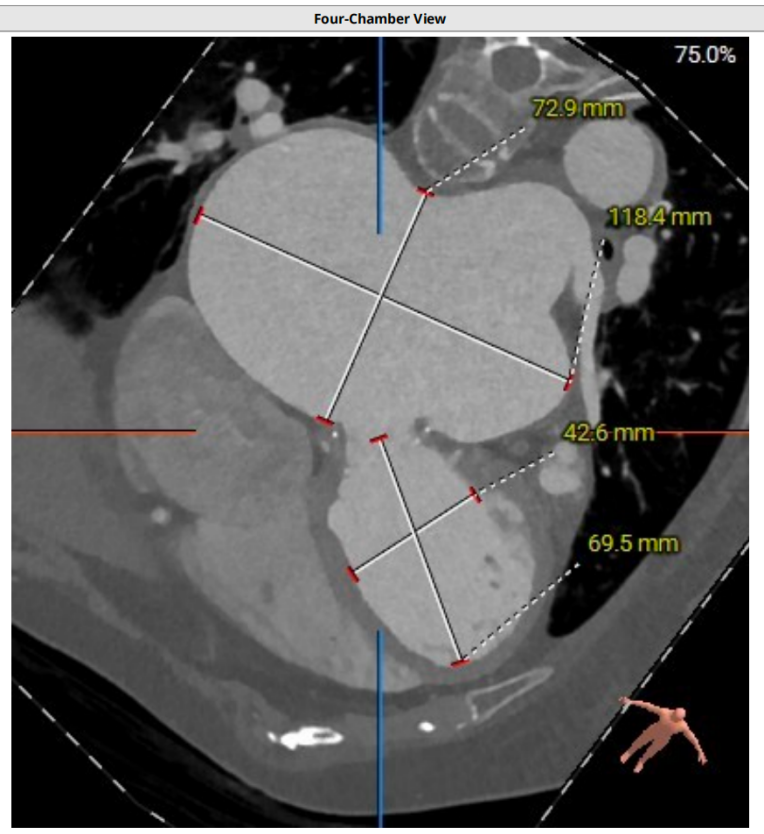

近日,大连医科大学附属第二医院心血管内科赵昕教授团队,联合超声医学科、麻醉科等多学科紧密协作,应用佰仁医疗Renatus®瓣膜系统,成功为一名高难度二尖瓣置换术后生物瓣衰败、二尖瓣重度反流的高龄患者,实施了经导管二尖瓣瓣中瓣置换术。该患者为77岁女性,因心脏重构,左右心房显著扩大,心功能差,再次接受传统外科开胸手术风险极高。面对这一挑战,赵昕教授团队组织多学科专家进行了深入研讨与全面评估,最终制定了经股静脉入路的微创介入手术方案。该方案旨在以最小的创伤,最大程度地确保手术的安全性及治疗的有效性。手术过程顺利,术后患者血流动力学即刻改善,取得了圆满成功,标志着大医二院在复杂结构性心脏病的微创介入治疗领域取得了又一重要突破。

二尖瓣生物瓣支架内径 26.5mm,结合瓣架形态、瓣架高度及手术记录,符合EPIC 27#。瓣中瓣治疗考虑选择25# 介入瓣膜。模拟25# 瓣膜植入,测得NEO-LVOT 面积155.8mm²,术后存在新流出道梗阻风险。左心耳尖端未见血栓。左心房增大73.4*118.7mm,房间隔未见增厚,未见明显钙化,靠后靠下房间隔穿刺点距二尖瓣水平高度27.7mm,房间隔穿刺点高度可。